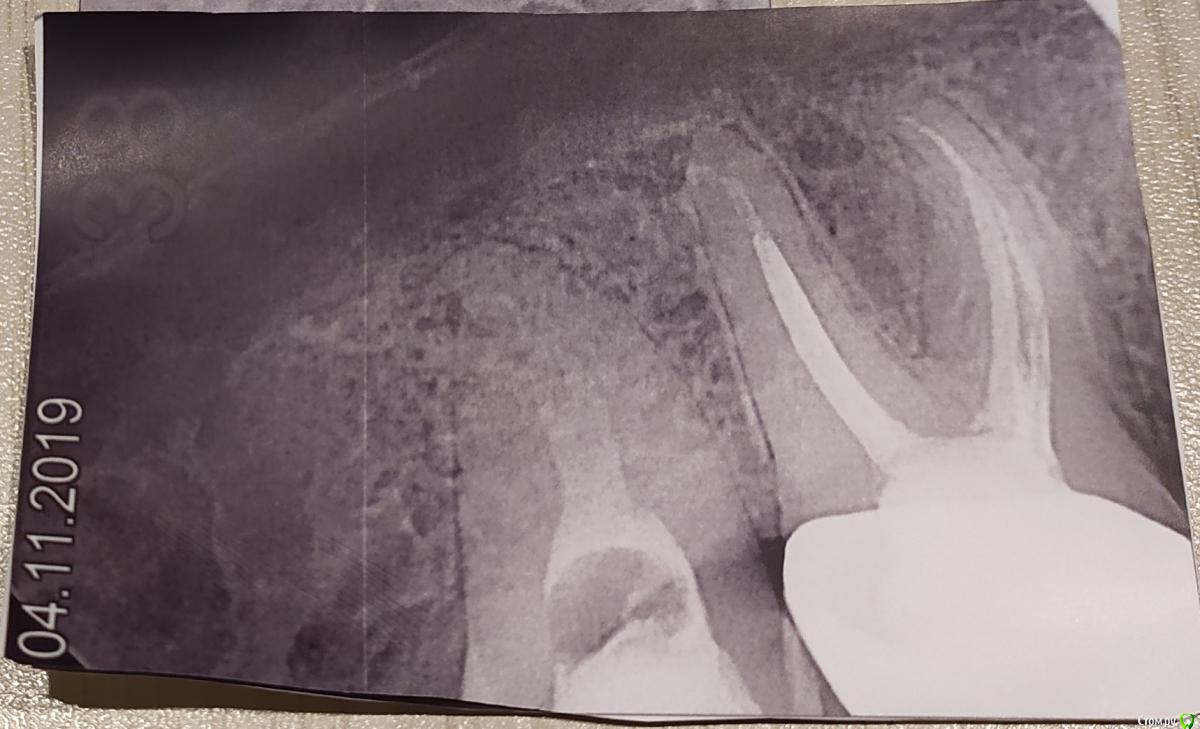

Stendal Опубликовано 8 ноября, 2019 Поделиться Опубликовано 8 ноября, 2019 Здравствуйте. Была пломба на зубе мудрости.Пошел к врачу, почистила каналы. Поставила какое-то лекарство под которым нерв должен был умереть. Зуб продолжал болеть. Пришел к врачу снова. Убрала этот материал, сказала полоскать содой с солью.На время открытия канала было полегче, но тем не менее болело. Пришел к ней через пару дней, поставила какой-то временный кальций-материал.Всеравно болит, отдает на ухо и висок.Сегодня сходил к другому врачу рассказал это всё, сказала, что не видит уже смысла в сохранении этого зуба.Так хотелось сохранить, не знаю что делать, сижу на кетанове.Подскажите пожалуйста. Фото прилагаю от 31.10 и 04.11. Ссылка на комментарий